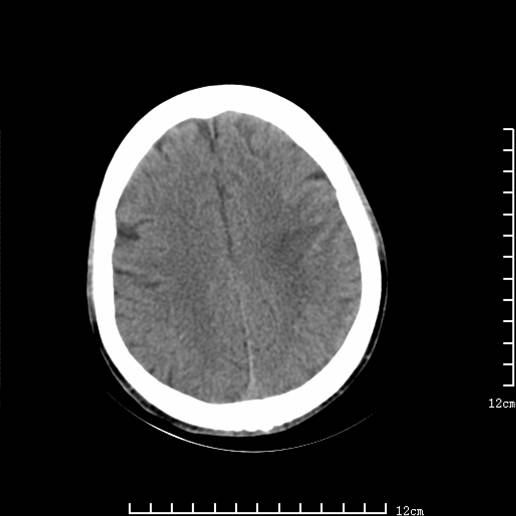

以下图像分别是3月25日凌晨及下午图像、3月27日、4月16日的ct图像。

3月25日下午

脑梗塞(左侧大脑中动脉分布区)。

1)左侧额颞顶叶、岛叶及基底节区(相当于左侧大脑中动脉供血区)大面积脑梗塞。2)右侧基底节区腔隙性脑梗塞。

大脑中动脉供血区大面积脑梗塞没有问题。

资料齐全,符合脑梗塞溶栓治疗后,血管再通而致的出血性脑梗塞。